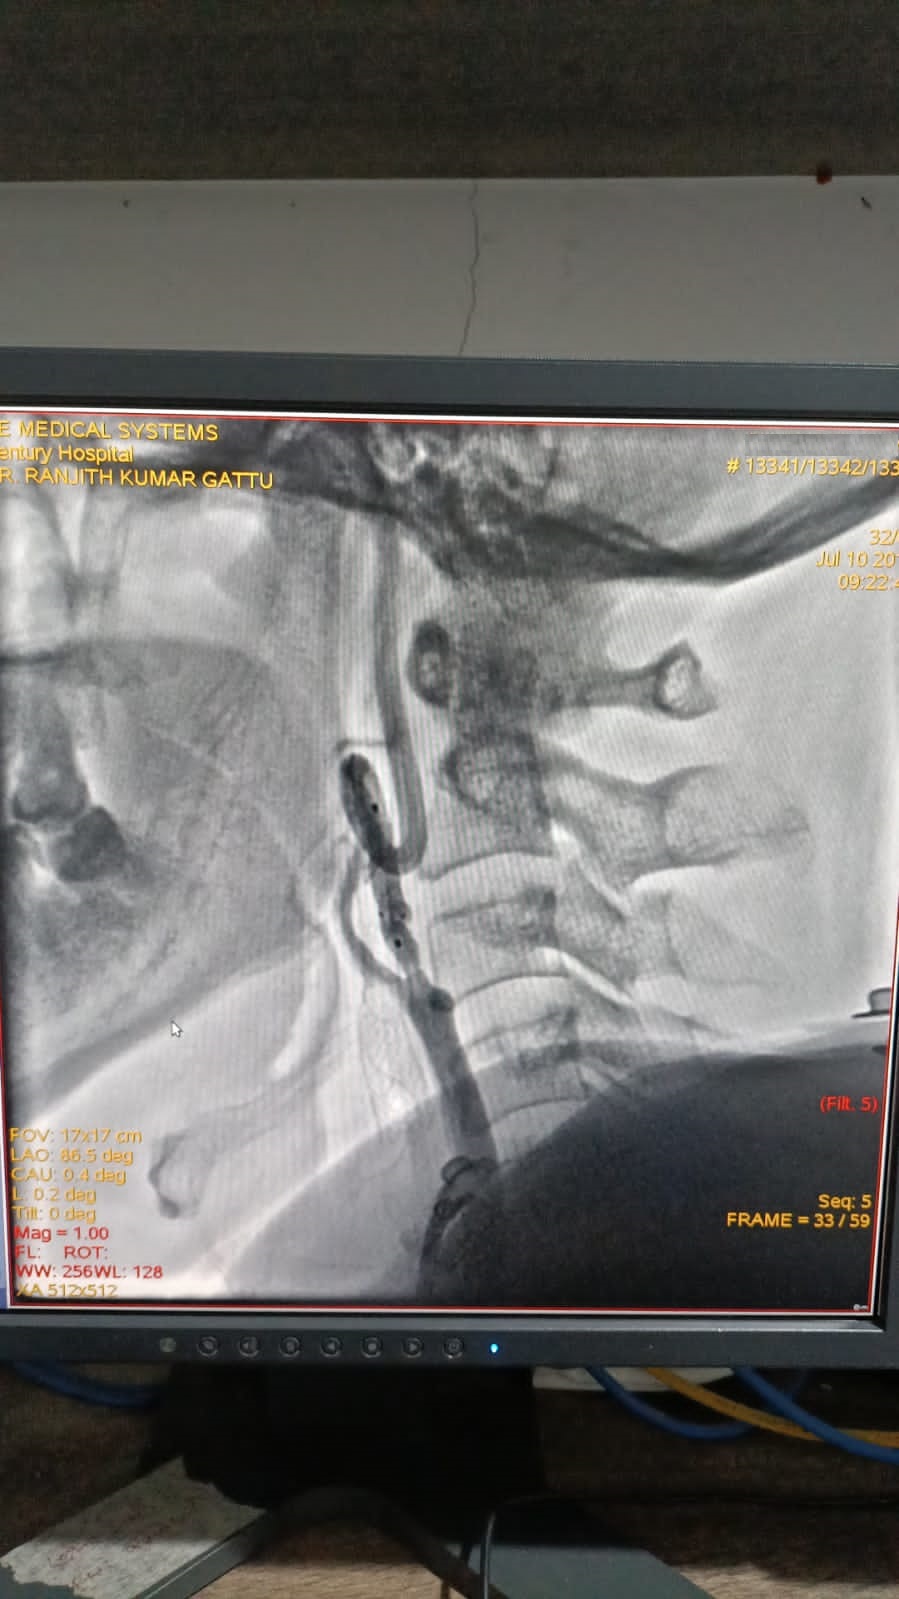

Left Coronary Artery